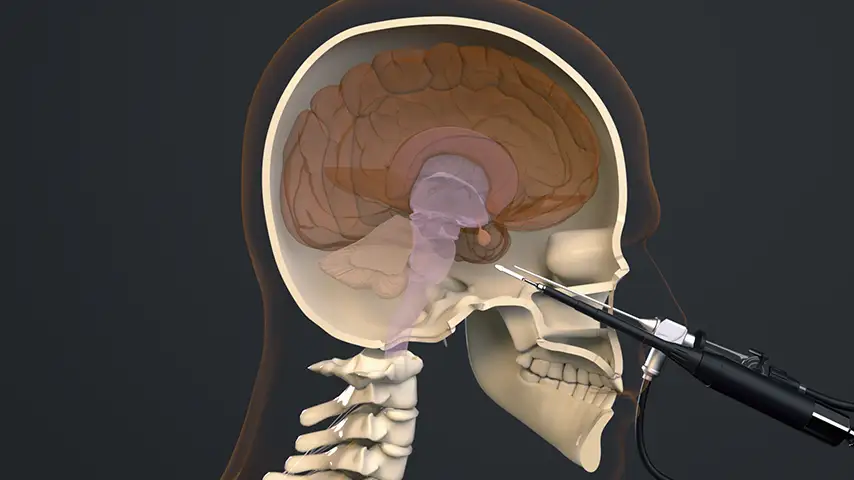

in Endoscopic and Microscopic Surgery

Posterior sphenoidotomy for pituitary tumor removal

Selective osteotomies, safety on soft tissues

Advantages over traditional tools

Reduced risk of damaging anatomically complex regions

Greater intraoperative control and bone management

Micrometric cut for minimal bone loss

Reduced heat generation to avoid bone necrosis